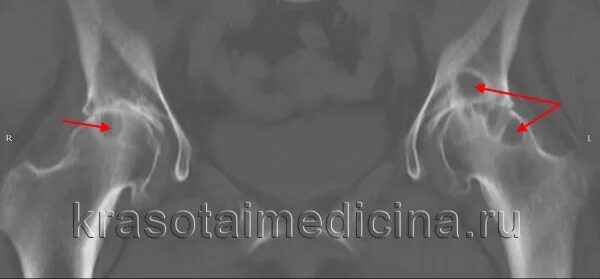

Некроз головки по мкб